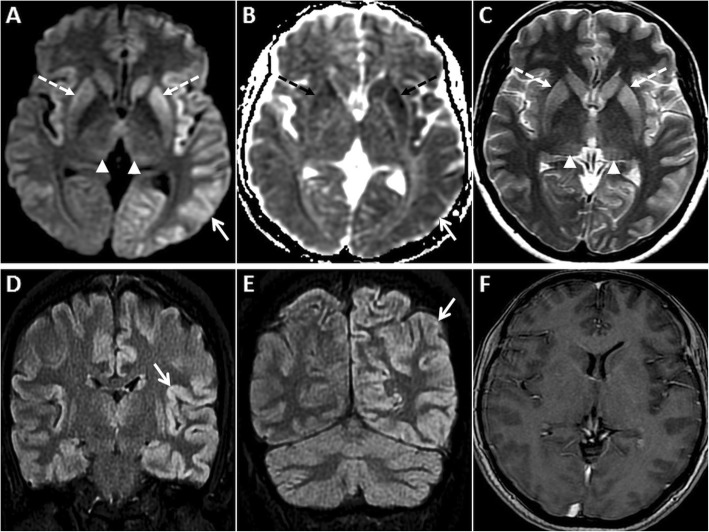

Fig. 10.

Pre- and post-contrast MRI of the brain in a 55-year-old male patient who presented with rapidly progressive dementia due to sCJD. GRD is seen in the left temporo-parieto-occipital region (arrows) and in the insular regions on axial DWI (a) and ADC image (b). Nearly symmetric restricted diffusion is also seen in the basal ganglia (dashed arrows) along with mild DWI hyperintensity in the pulvinar nuclei (arrowheads). Axial T2W image (c) shows T2 hyperintensity in the basal ganglia (dashed arrows) and pulvinar nuclei (arrowheads). Sequential anteroposterior FLAIR images (d, e) demonstrate the extent of the cortical signal abnormality (arrows). No enhancement is seen in these regions on axial post-contrast T1W image (f)